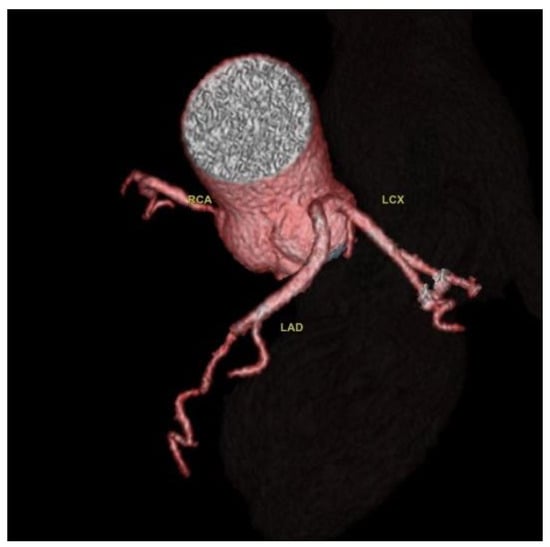

Nine cases of coronary anomalies with intramuscular bridging of the left anterior descending artery were found (Figure 6).

In coronary intramyocardial bridging, a portion of the epicardial coronary pathway is covered by heart muscle; the artery most affected by this condition is the LAD artery [1]. Nine cases of coronary artery intramuscular bridging were detected, and the findings are consistent with the scientific literature; all cases included the left anterior descending artery. Intramuscular bridges are frequently an incidental encounter in CCTA examinations, and only some of them associate systolic compression with a possible reduction in myocardial perfusion. Intramuscular bridges are sometimes associated with atypical angina pectoris. The impact of myocardial bridges on the risk of myocardial infarction is debatable. They are generally considered benign conditions, but the length and depth of the intramyocardial bridge may influence the degree of coronary dysfunction, with some studies showing an association of myocardial bridges with increased risk of myocardial infarction [27,28,29].

Figure 6. Intramuscular bridging of the left anterior descending artery. (a) CCTA oblique sagittal maximum intensity projection image of the LAD route shows intramuscular bridging of the left anterior descending artery in the second segment for a 30 mm distance and 3 mm depth; (b) CTAA volume rendered 3D images show the LAD in the atrioventricular groove entering an intramural route; (c) CCTA curved planar reformatted image of the LCA entering an intramural route; (d) CCTA vessel cross-section image of the LCA with intramural course.